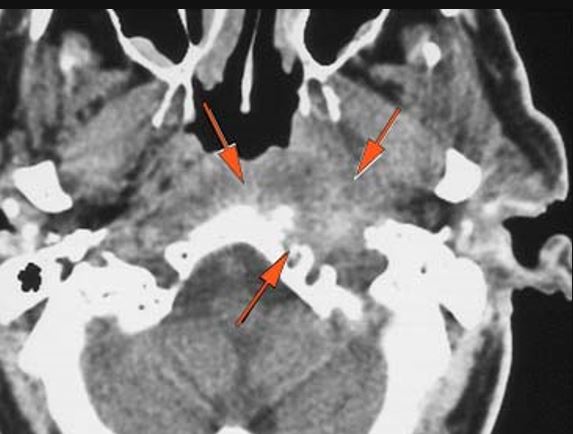

There is likely meningitis involving the inferior temporal lobe or adjacent cerebellum or more remote meningeal sites. [Yes/No]

There is brain edema and/or evolving abscess present or, specifically, involving the inferior temporal lobe or adjacent cerebellum. [Yes/No]

There is evidence of thrombosis, thrombophlebitis or other occlusive or inflammatory process of the sigmoid sinus, transverse sinus, the vein of Labbe’ or jugular bulb or vein. [Yes/No]